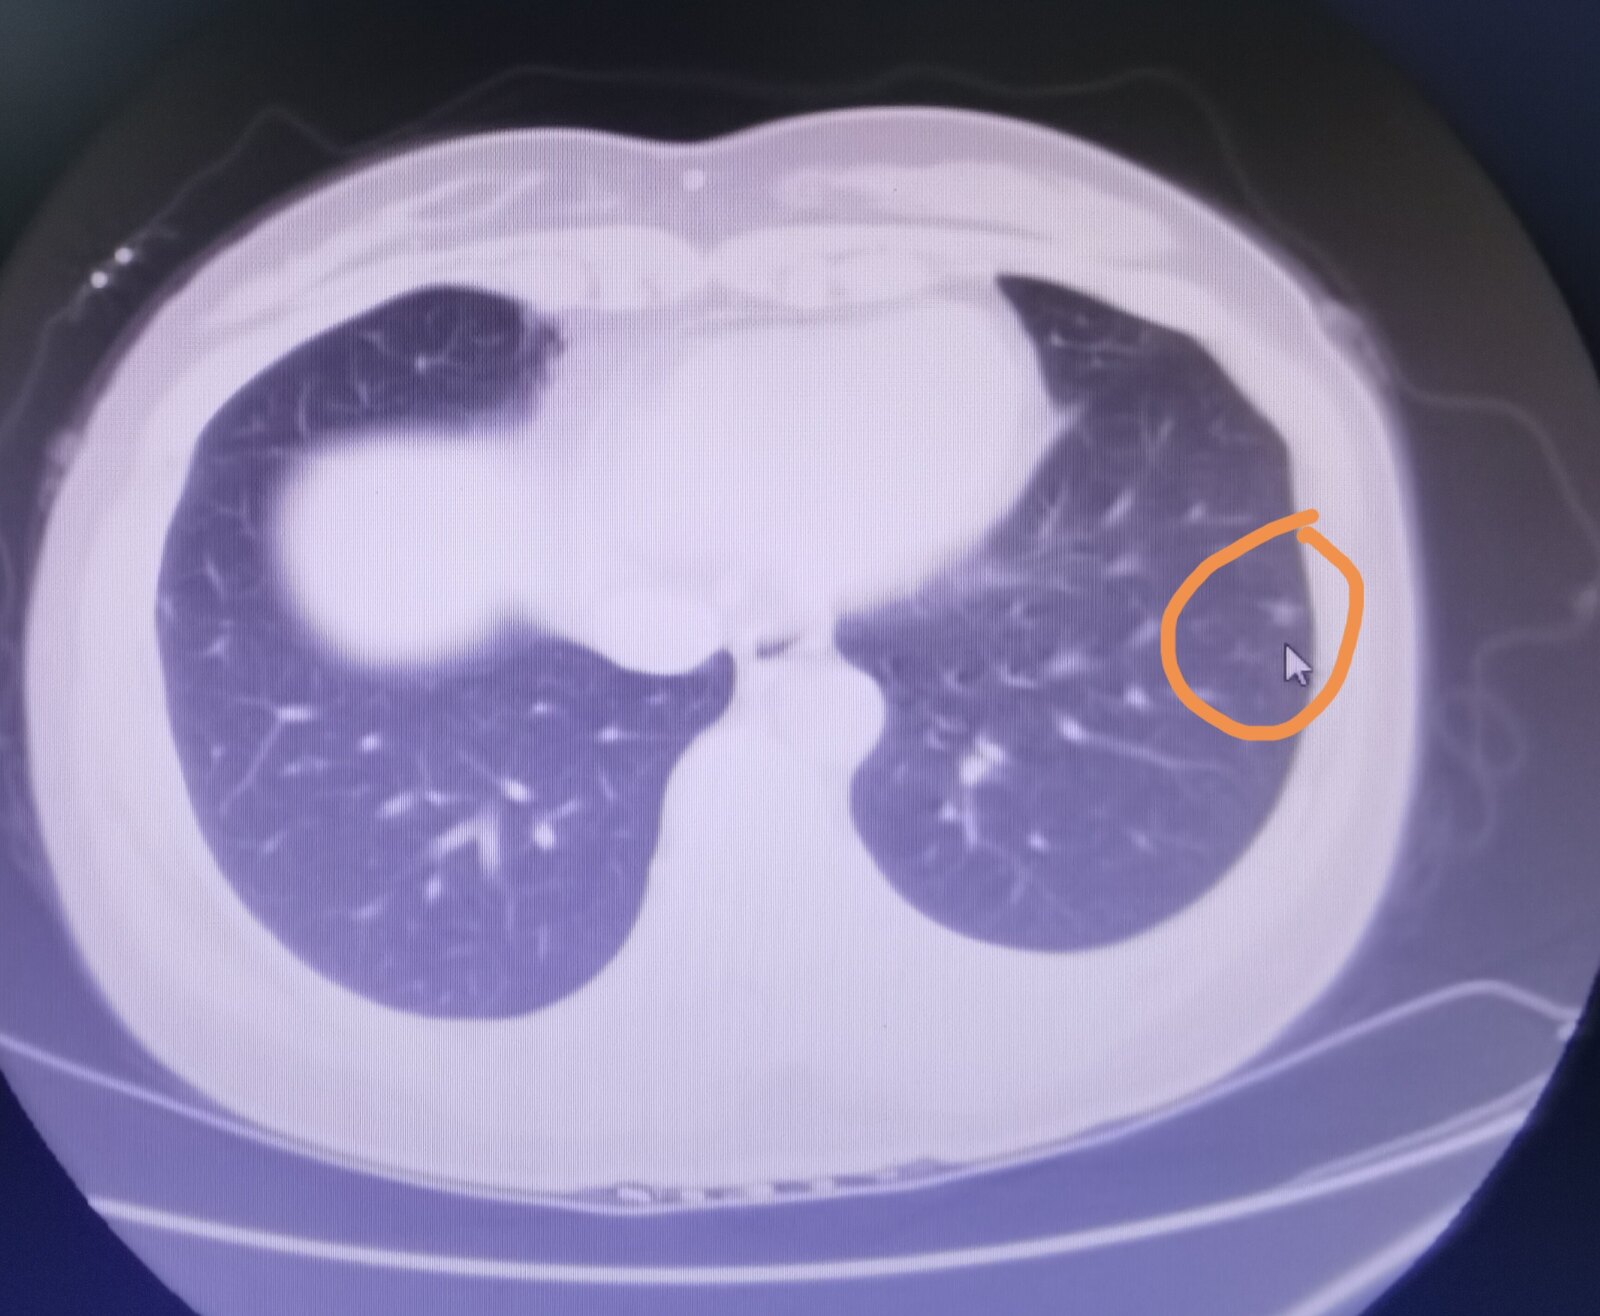

我登录系统看到了徐女士的片子,她肺部有两个实性的结节,一大一小,大的在左肺,小的在右肺,但大的那个也就5毫米左右,看起来像是肺内的淋巴结,是良性的结节。我还注意到在徐女士的胸部皮肤下面有一个引流管,我问她这个引流管是什么情况,她说自己是枕大池囊肿,做的管子引流。这根管子和肺里两个结节没有什么联系。

徐女士的症状和这两个结节没有什么太大的关系,如果疼痛严重,可以看看骨科或者心脏科,肺部这两个结节,继续观察就可以。